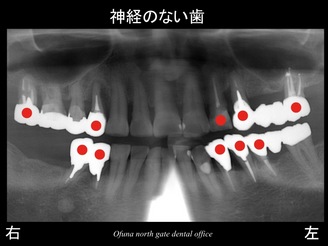

それでは 早速 症例のレントゲンを見ましょう。

以下が初診時のレントゲンです。

『下顎右側の奥歯が欠損しており、噛めない!』

『上顎右側の奥歯がグラグラしている!』

との問題で来院されました。

この患者様で大きな問題は、神経がない歯が多いことです。

このブログでも良く書いていますが、神経のない歯は非常に脆く、通常の噛む力でも折れてしまう確立が非常に高いのです。

歯根破折 です。